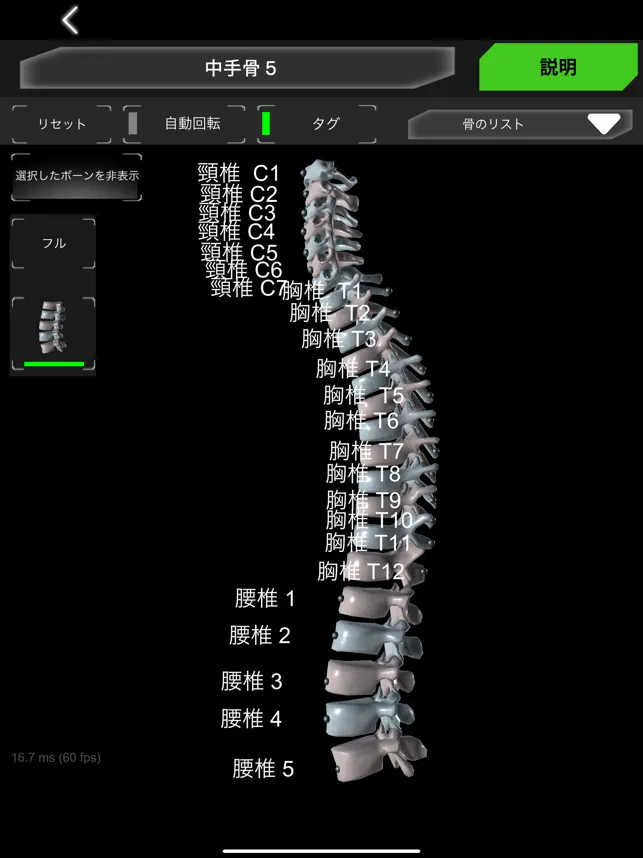

人間の骨格の解剖学に関する情報を 3 次元モデルで示します。

骨システムの 3 次元モデルとそれらすべての説明が表示されます。

頭蓋骨、背骨、肋骨、胸骨、大腿骨、脛骨、腓骨などの各骨を触るとその情報が表示されます。